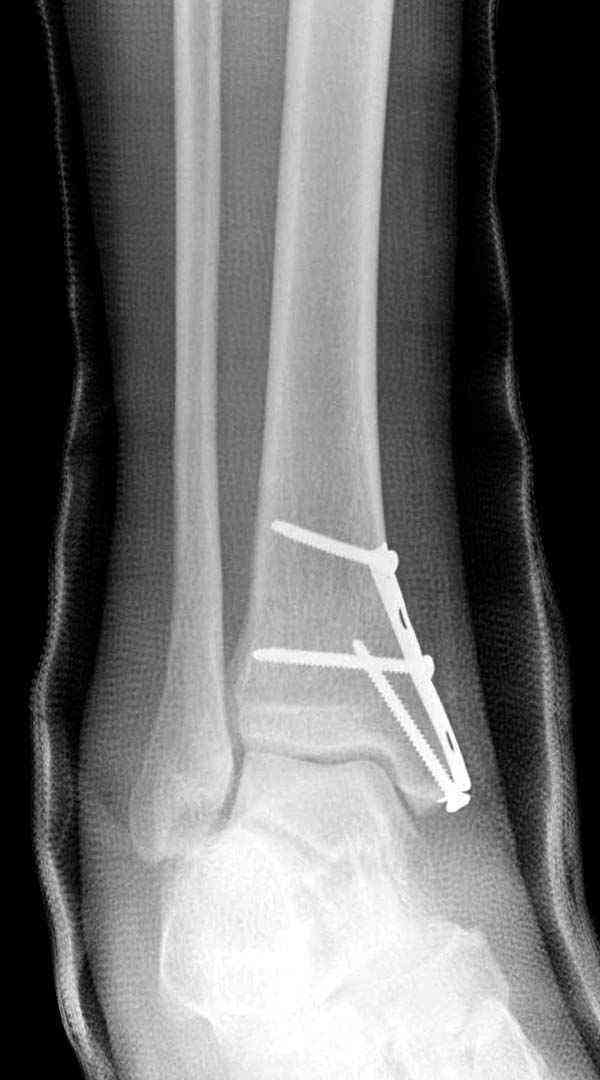

Во всех руководствах АО имеется описание техники применения низкопрофильных пластин 1/3 трубки, которые могут быть применены для фиксации наружной лодыжки. Фиксацию проводят кортикальными 3.5 мм шурупами, и если дистальная фиксация недостаточная, тогда усиливают конструкцию созданием hook plate. Сгибая конец пластины на последнем отверстии, внедряют его в дистальный отдел, и тем самым создается дополнительная фиксация.

Современные преконтурированные пластины не имеют таких недостатков, и разделяются на правые и левые, а также на латеральные и задние. Множественные дистальные шурупы 2.7 мм уменьшают подкожное раздражение, и такой имплант можно оставить на долгий срок без удаления.

Для молодых достаточным бывает обычная лодыжечная пластина без блокировки, и только у пожилых с остеопорозом лучше взять полиаксиальные пластины с угловой стабильностью.

Медиальная лодыжка фиксируется каннюлированными лодыжечными шурупами перкутанно, а неточная репозиция (интерпозиция) является показанием к открытой технике. При больших вертикальных фрагментах нужны противоскользящие медиальные пластины.

Здесь несколько частных случаев: перелом голеностопа со сравнительными снимками и разрыв синдесмоза, а также медиальная Hook пластина.